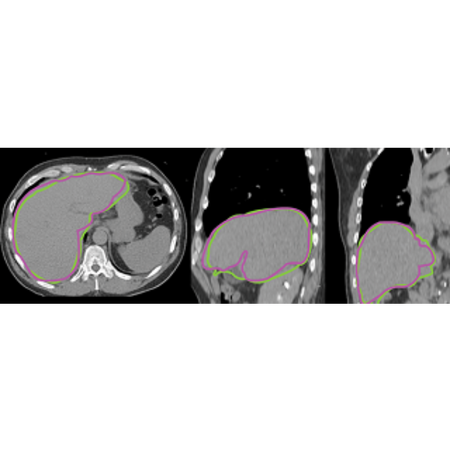

- Vendor-neutral Y90 microspheres dose calculation.

With MIM SurePlan LiverY90, there is no longer a need to wait for the 3D lab to provide you with liver volumes or use software not designed for this purpose. Through atlas segmentation, you can significantly reduce the time required to generate liver volumes. A recent study in the Journal of Nuclear Medicine demonstrated a 70% reduction in time compared to manual outlining of the liver. Industry-leading segmentation tools are also available for tumors and the lungs.